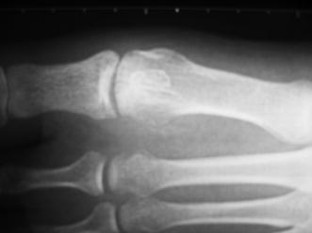

Fig. 2